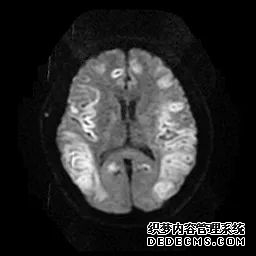

脑MRI显示尾状核、扁豆状核和脑梗头部T2/FLAIR呈双侧对称异常高信号。扩散限制涉及这些区域,其特征是扩散加权DWI(B-1000)上的高强度,ADC图上相应的减弱强度。

印象:通过将这些成像模式与临床和实验室检查结果相结合,就有可能得出低血糖性脑病。

影像影响内囊后肢、大脑皮层(特别是枕叶和岛叶)、海马和基底节区,常是双边对称性的。